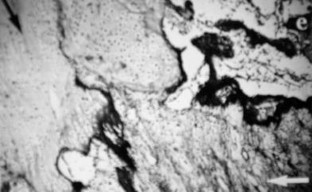

Fig. 4